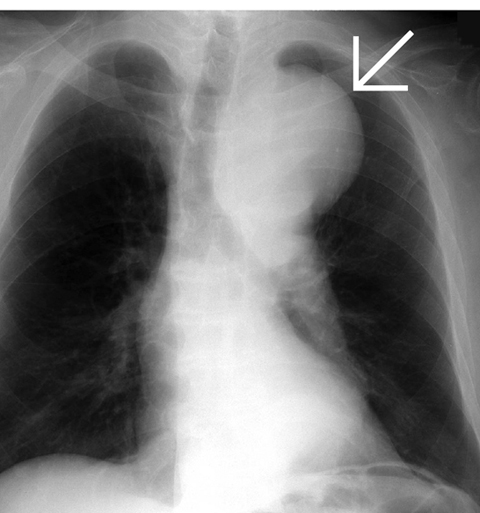

優先配送 【楽天市場】イラストレイテッド大動脈瘤手術 ブックスドリーム 参考書専門店 秀雄: 安達 医学一般